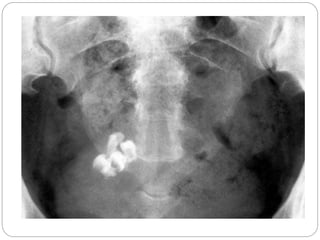

 Calcification has been noted to occur in over 50%

of Cases

 Calcification helps in suggesting a diagnosis of

neurogenic tumour

Cystic neuroblastoma/ Ganglioneuroma(rare)  Overhalf of them arise in the adrenals, but 30% can arise  from sympathetic tissue elsewhere in the abdomen  Calcification has been noted to occur in over 50% of Cases  Ganglioneuroma is a mature form of neurogenic tumour.  Calcification helps in suggesting a diagnosis of neurogenic tumour